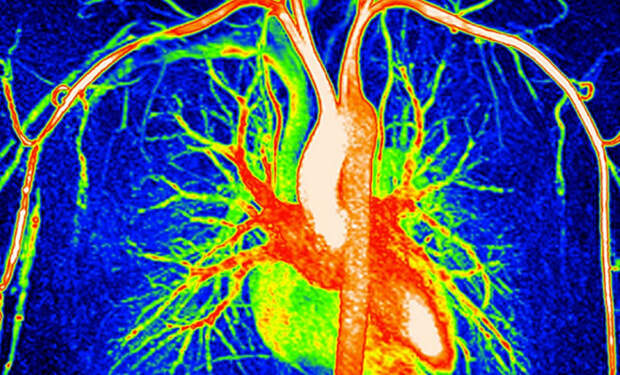

Авторы работы из Академии наук Китая собрали образцы тканей восьми различных систем организма у 76 человек в возрасте от 14 до 68 лет. Анализ показал: с возрастом растет уровень 48 белков, связанных с заболеваниями, а наиболее резкие изменения начинаются между 45 и 55 годами. Особенно сильно стареет аорта — главная артерия, по которой кровь выходит из сердца. Один из обнаруженных белков, вводимый мышам, вызывал у них явные признаки преждевременного старения.

Авторы работы из Академии наук Китая собрали образцы тканей восьми различных систем организма у 76 человек в возрасте от 14 до 68 лет. Анализ показал: с возрастом растет уровень 48 белков, связанных с заболеваниями, а наиболее резкие изменения начинаются между 45 и 55 годами. Особенно сильно стареет аорта — главная артерия, по которой кровь выходит из сердца. Один из обнаруженных белков, вводимый мышам, вызывал у них явные признаки преждевременного старения.